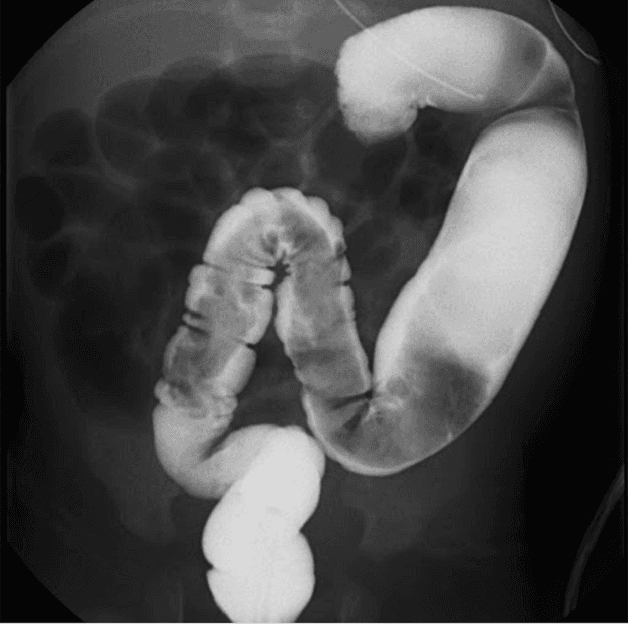

4.1 Chụp X-quang chẩn đoán phình đại tràng

Chụp X-quang là phương pháp hiệu quả giúp chẩn đoán phình đại tràng ở trẻ nhỏ. Kỹ thuật chụp X-quang có sử dụng chất cản quang sẽ cho thấy đoạn ruột hẹp và đoạn ruột giãn.

Chụp X-quang chẩn đoán phình đại tràng